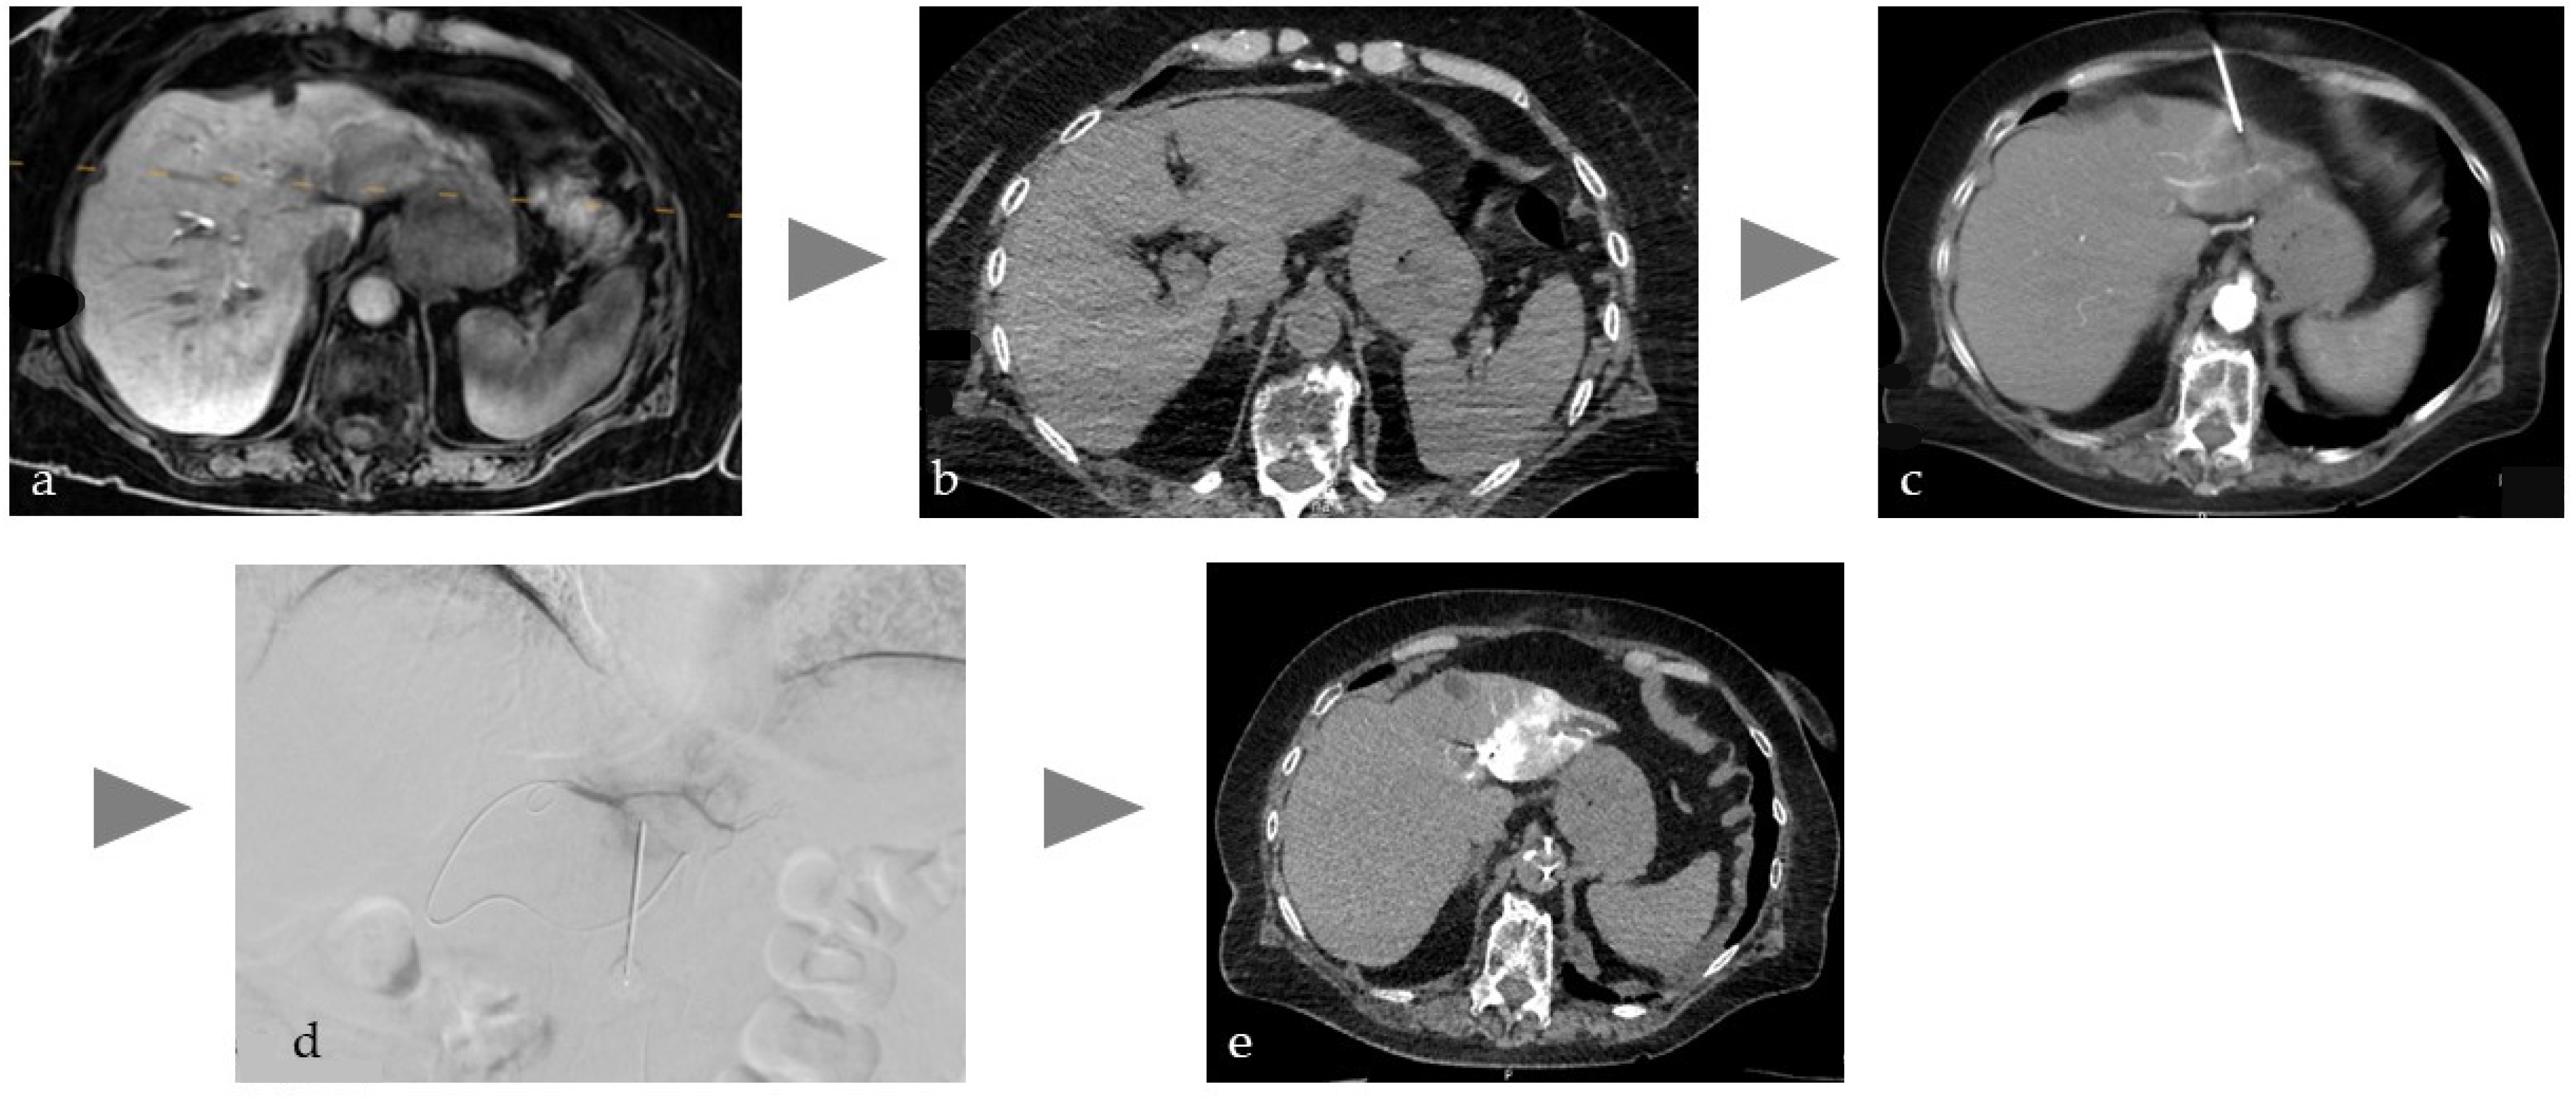

Figure 3. Typical workflow in the percutaneous treatment of a type 2 endoleak after EVAR of an abdominal artery aneurysm. (a) Planning CT in prone position with intra-arterial injection of 150 mL volume, with a dilution of 1:10 corresponding to approx. 15 mL CM to detect the endoleak (white arrow) in the aortic sac, (b,c) translumbar CT-guided fine needle puncture, (d) after insertion of the guide wire, placement of the microcatheter under fluoroscopic view, (e) controlled embolization of the endoleak with liquid (Onyx18) under fluoroscopic view.